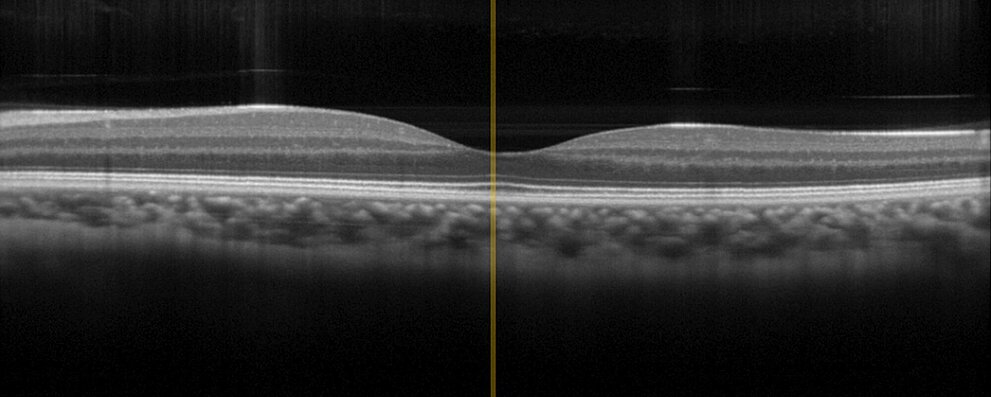

L'endoscopia e la diagnostica in vivo sono tra le tecnologie mediche più sofisticate poiché vengono applicate all'interno o sull'organismo vivente. Qui è indispensabile la massima affidabilità. I decenni di esperienza di PI come fornitore di aziende nella tecnologia medica e i 30 anni di esperienza come produttore di componenti piezoelettrici sono valori essenziali che PI apporta nello sviluppo e nella fabbricazione di assiemi e sottosistemi. A titolo d'esempio, PI offre più di un azionamento per la messa a fuoco variabile degli endoscopi chip-on-the-tip. Per la tomografia a coerenza ottica (OCT) con le sue applicazioni in oftalmologia o dermatologia, PI offre diverse tecnologie di azionamento che possono essere adattate alle esigenze specifiche del dispositivo, come le dimensioni o la corsa, per un posizionamento preciso dell'ottica.